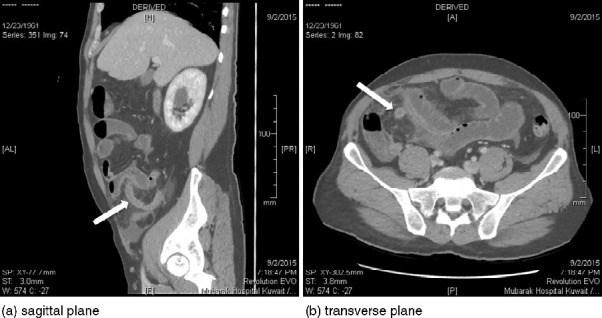

Acute appendicitis is the most common surgical condition with which patients present in emergency departments worldwide. It is also a rare cause of intestinal obstruction. Here, we report a case of a 53-year-old man who presented with a clinical picture of mechanical small bowel obstruction. Leucocytosis was not demonstrated on the routine blood investigation in our case, in contrast to the findings for most patients with acute appendicitis. Acute appendicitis, as the cause of the intestinal obstruction, was diagnosed by computed tomography of the abdomen. The patient was treated using diagnostic laparoscopy and laparoscopic appendectomy. This case was compared with those previously reported in the medical literature to determine the frequency of the case and the surgical management.